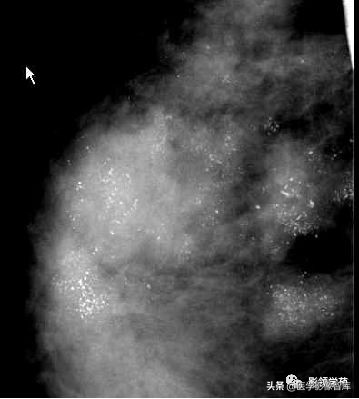

细小多形性钙化

阶段性或线性,大小和形状多变,<0.5mm, 25-40%为恶性。

BI-RADS5,手术证实为DCIS。

阶段性分布,分为BI-RADS5,手术证实为高级DCIS。